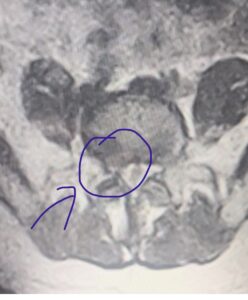

De acuerdo con la resonancia magnética, la hernia es de gran tamaño y comprime la raíz del nervio ciático en la extremidad inferior derecha que toca la médula, razón por la cual, se requiere de una intervención quirúrgica para corregir la sintomatología con un espaciador U de titanio, que le ayudará a recuperar su salud.